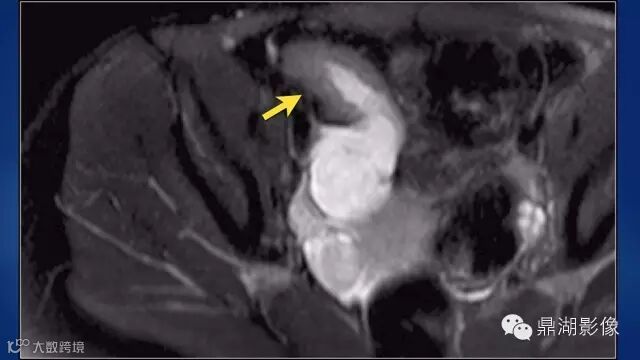

what's the meaning of fat halo sign?

粘膜下水肿或脂肪沉积,可致肠壁内呈低密度层(halo征),其最初用来描述溃疡性结肠炎,是良性肠道病变的结果,无特异性,也可存在于放射性肠炎,移植-受体疾病和慢性缺血性肠炎以及单性的肥胖症患者。

Fat halo aslo can be seen in normal terminal ileum.

ULCer